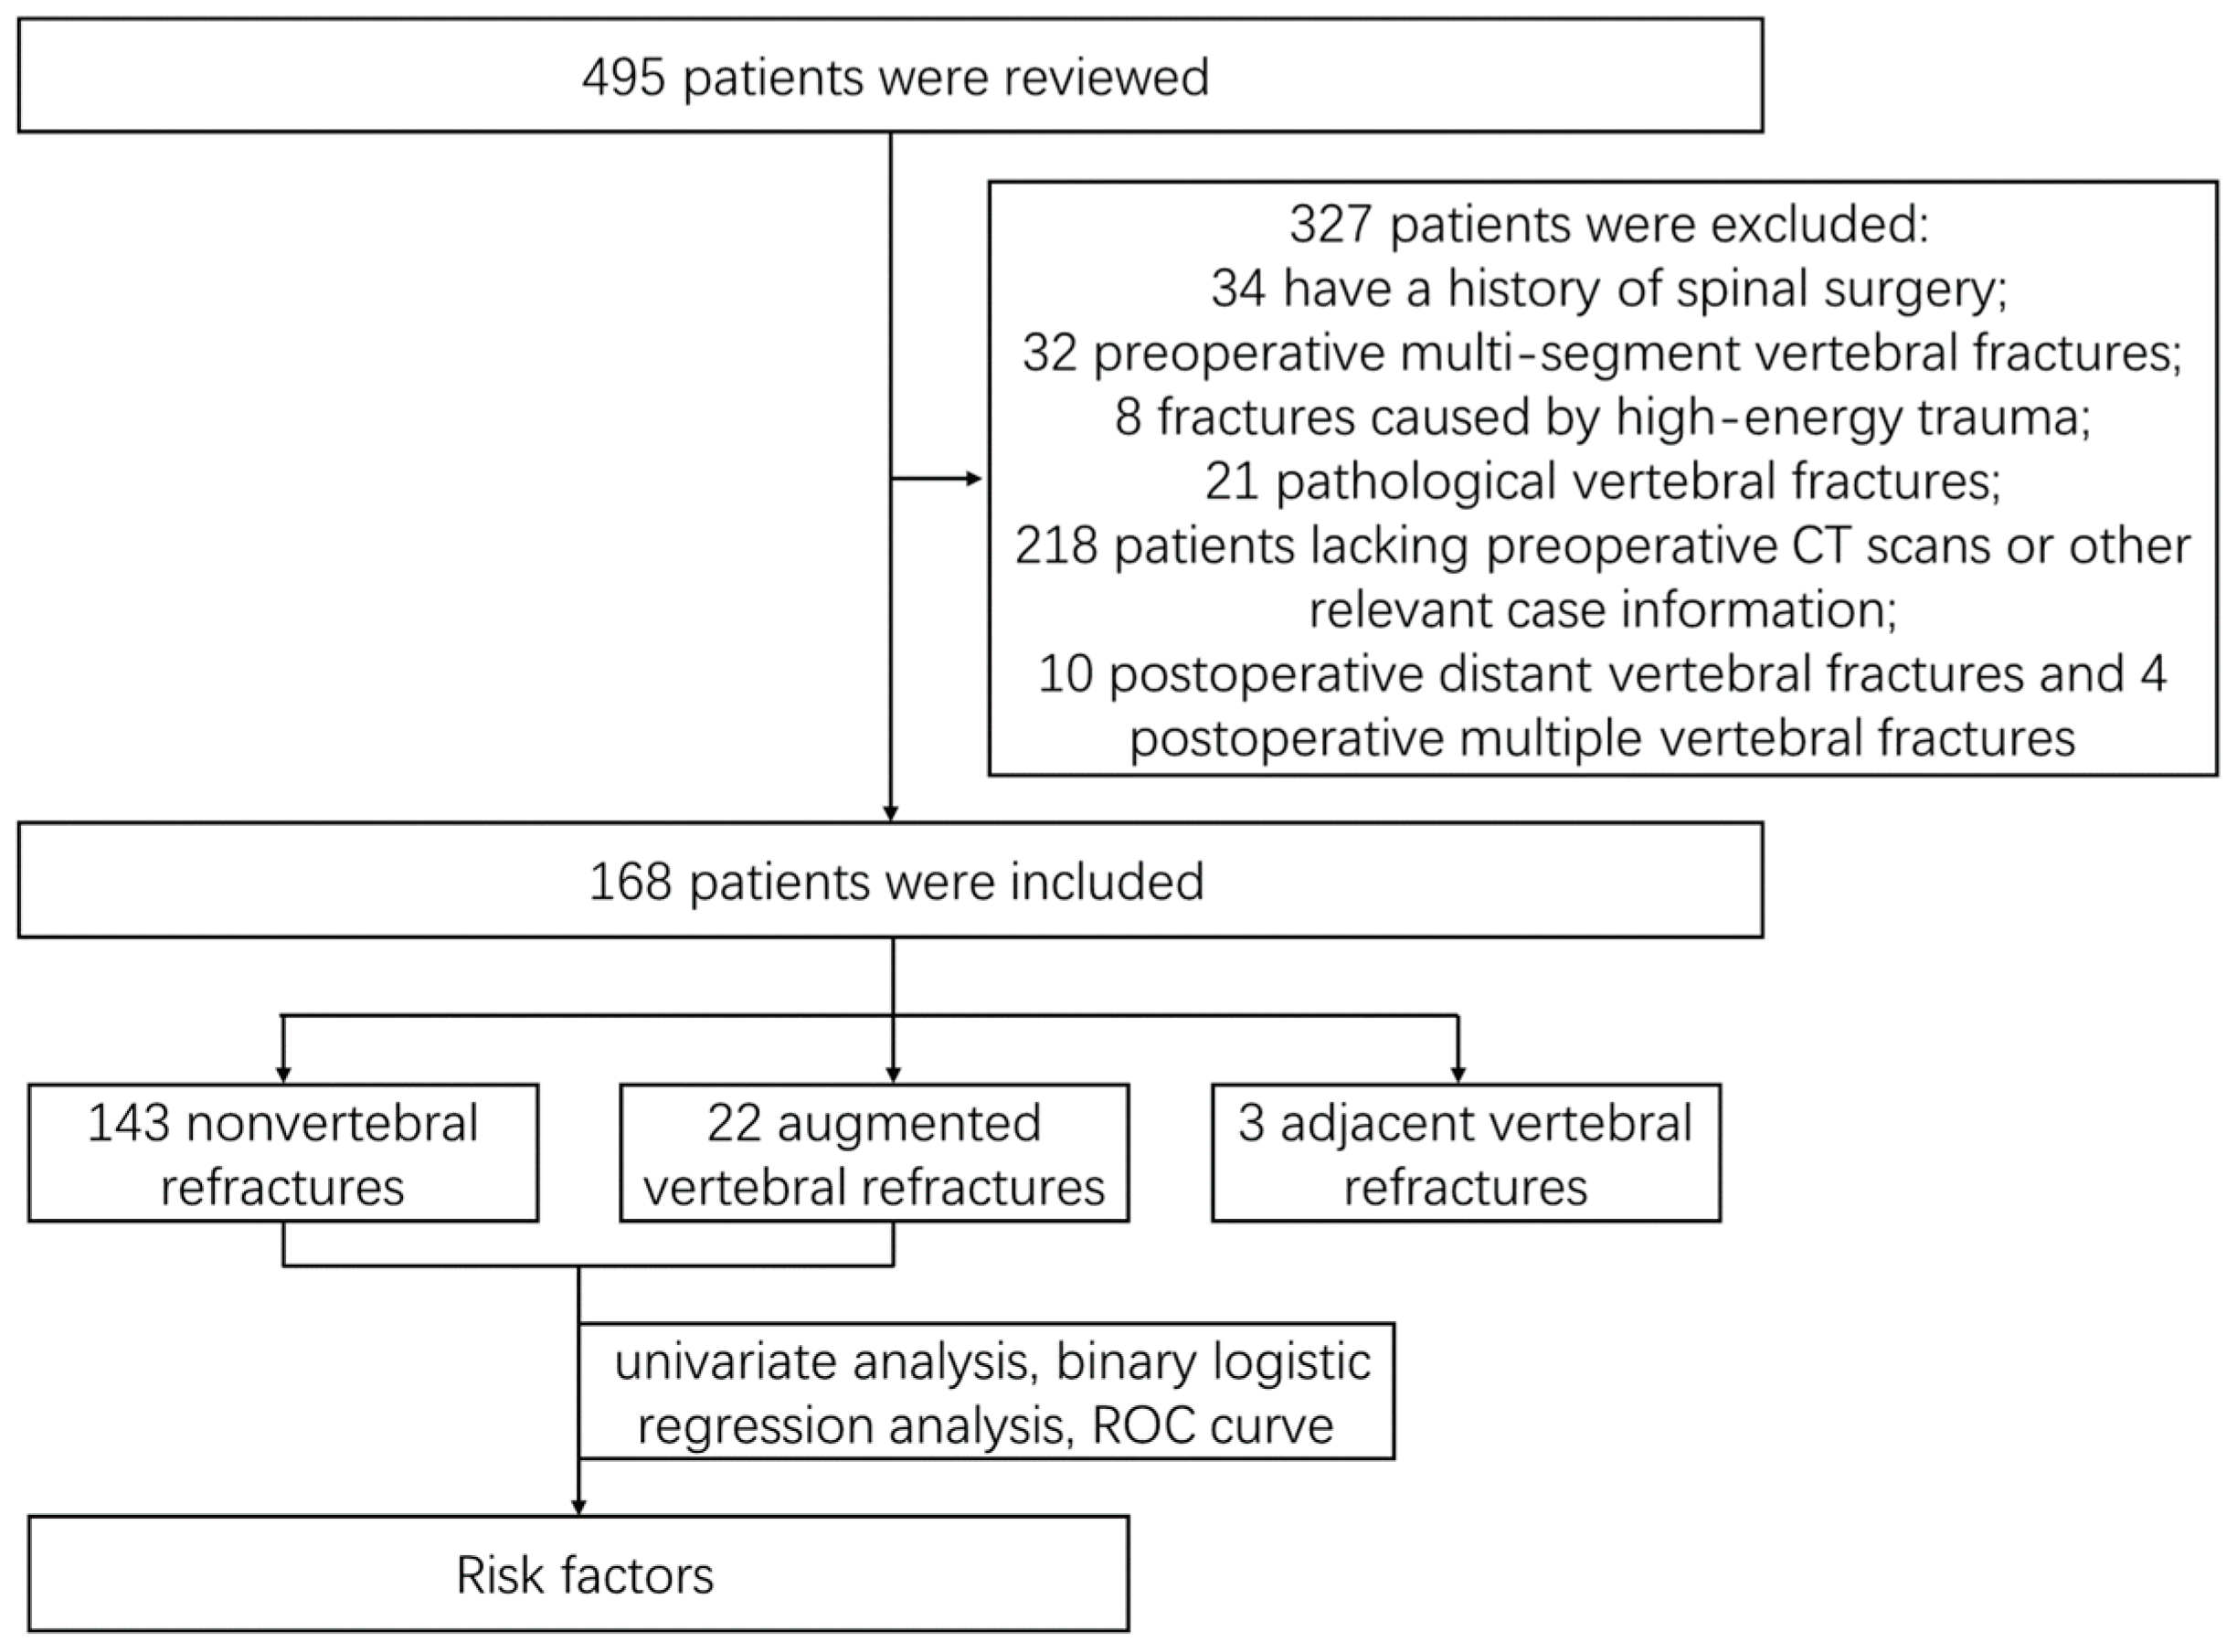

2. Materials and Methods

2.1. General Data

3.1. General Situation

3.2. Augmented Vertebral Refractures